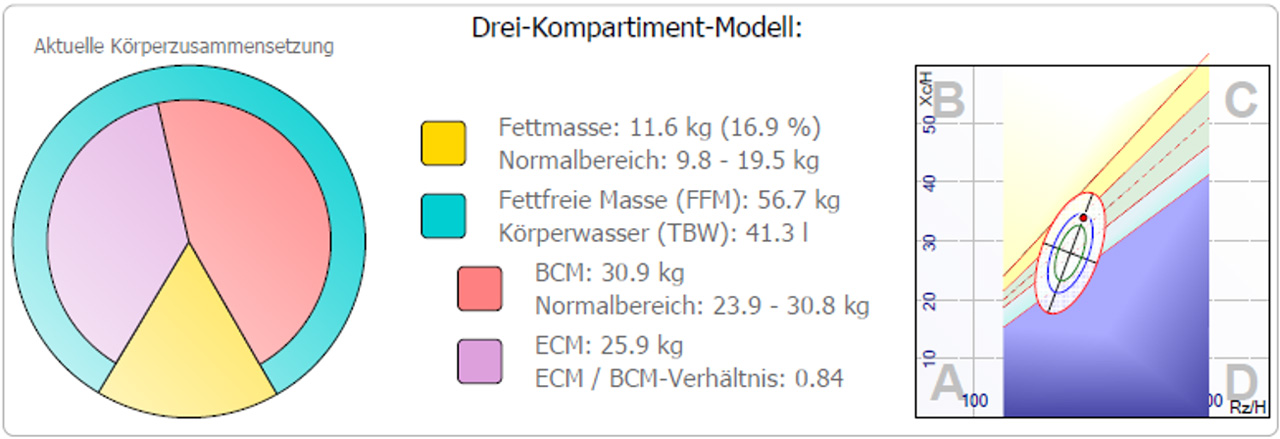

Darstellung des Dreikompartiment Models

In dieser Darstellung kann in einem einfachen Kuchenmodell schnell die Verteilung der Massen in den drei Kompartimenten dargestellt werden.

Im linken Diagramm werden auf der rechten Seite die Hydrationsverhältnisse mit unterschiedlichen Farben veranschaulicht: blau steht für überwässert, grün für normale Hydration und gelb für dehydriert.